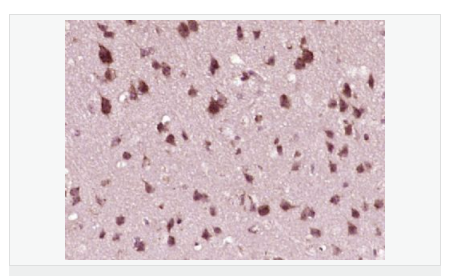

產(chǎn)品應(yīng)用WB=1:500-2000 ELISA=1:5000-10000 IHC-P=1:100-500 IHC-F=1:100-500 Flow-Cyt=1ug/test ICC=1:100-500 IF=1:50-200 (石蠟切片需做抗原修復(fù))

細(xì)胞定位細(xì)胞核 細(xì)胞漿